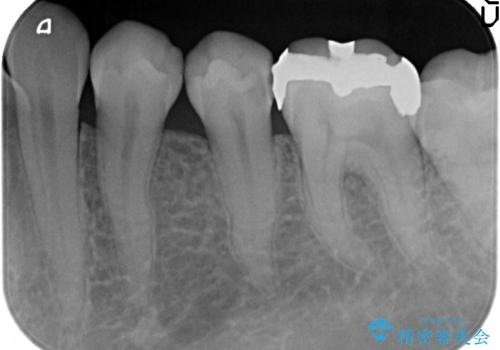

セラミックインレー 他院にて歯の神経治療が必要と言われた虫歯

- 他院にて左下5の虫歯治療を行おうとしたところ、歯の神経治療をすると言われたため、できれば神経を残せないかと当院にいらっしゃった方の症例です。

自発痛・持続痛等の症状がなく、露髄(歯の神経が露出してしまうこと)することなく虫歯の除去を完了したため、しばらく経過観察を行った後に神経治療をすることなく、セラミックインレーによる修復を行うことができました。

※神経治療となる可能性は事前にお話しした上で治療を行っております。